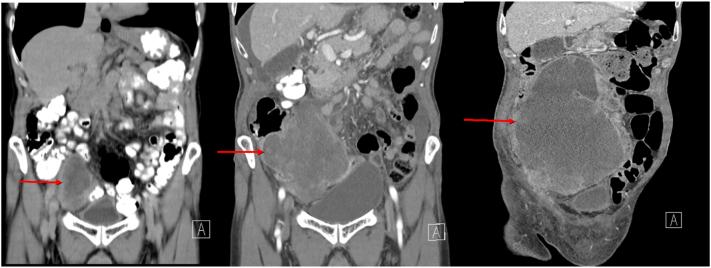

We report a case of an 83-year-old-male who presented with a one-month history of abdominal pain. A computer tomography (CT) scan identified a lower pelvic mass measuring 7.39 cm × 5.40 cm. A biopsy was done which revealed appendiceal carcinoma. A plan for radiotherapy to reduce the tumor size was made and the patient was discharged. However, the patient returned after three weeks due to worsening abdominal pain and a CT scan identified a significant enhancement in the tumor size. The patient underwent debulking surgery. Pathology of the specimen identified adenocarcinoma of the appendix.

A rapidly growing carcinoma of the appendix is rare as they are known to have a slow growth rate. A swift diagnosis and intervention are required as these rapidly enhancing neoplasms in the abdomen can become unresectable and metastasize. Although there are various methods of treatment for appendiceal carcinomas, the rapid growth rate and lack of response to radiation required debulking surgery.